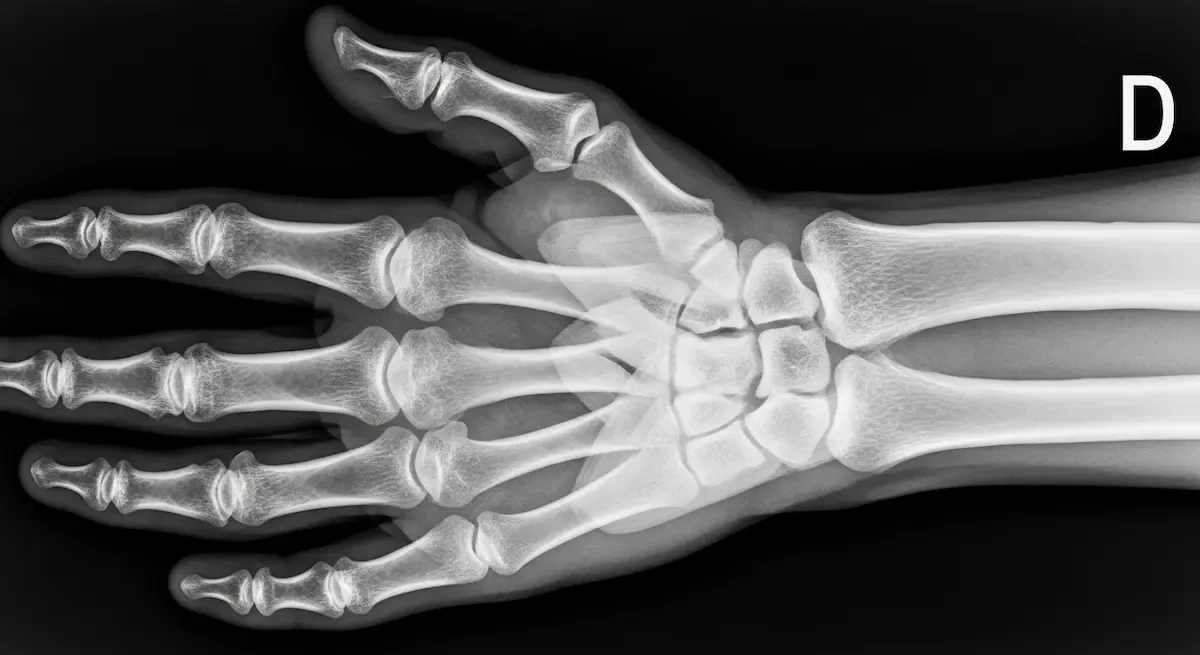

A mão humana é composta por 27 ossos, inúmeros músculos, tendões e, claro, uma complexa rede de ligamentos.

Esses ligamentos podem ser classificados de diversas formas, mas, em termos práticos, são divididos em:

- Ligamentos intrínsecos: conectam os ossos dentro da própria mão, como os ligamentos intercarpais que unem os ossos do carpo, ou os ligamentos colaterais das articulações metacarpofalângicas e interfalângicas.

- Ligamentos extrínsecos: conectam os ossos do carpo ao rádio e à ulna, como o ligamento radiocarpal dorsal e o ligamento radiocarpal volar.